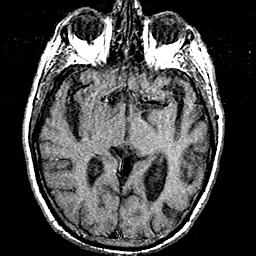

T1 - weighted MR -- Slice #21

[Home][Help][Clinical] Slice 21